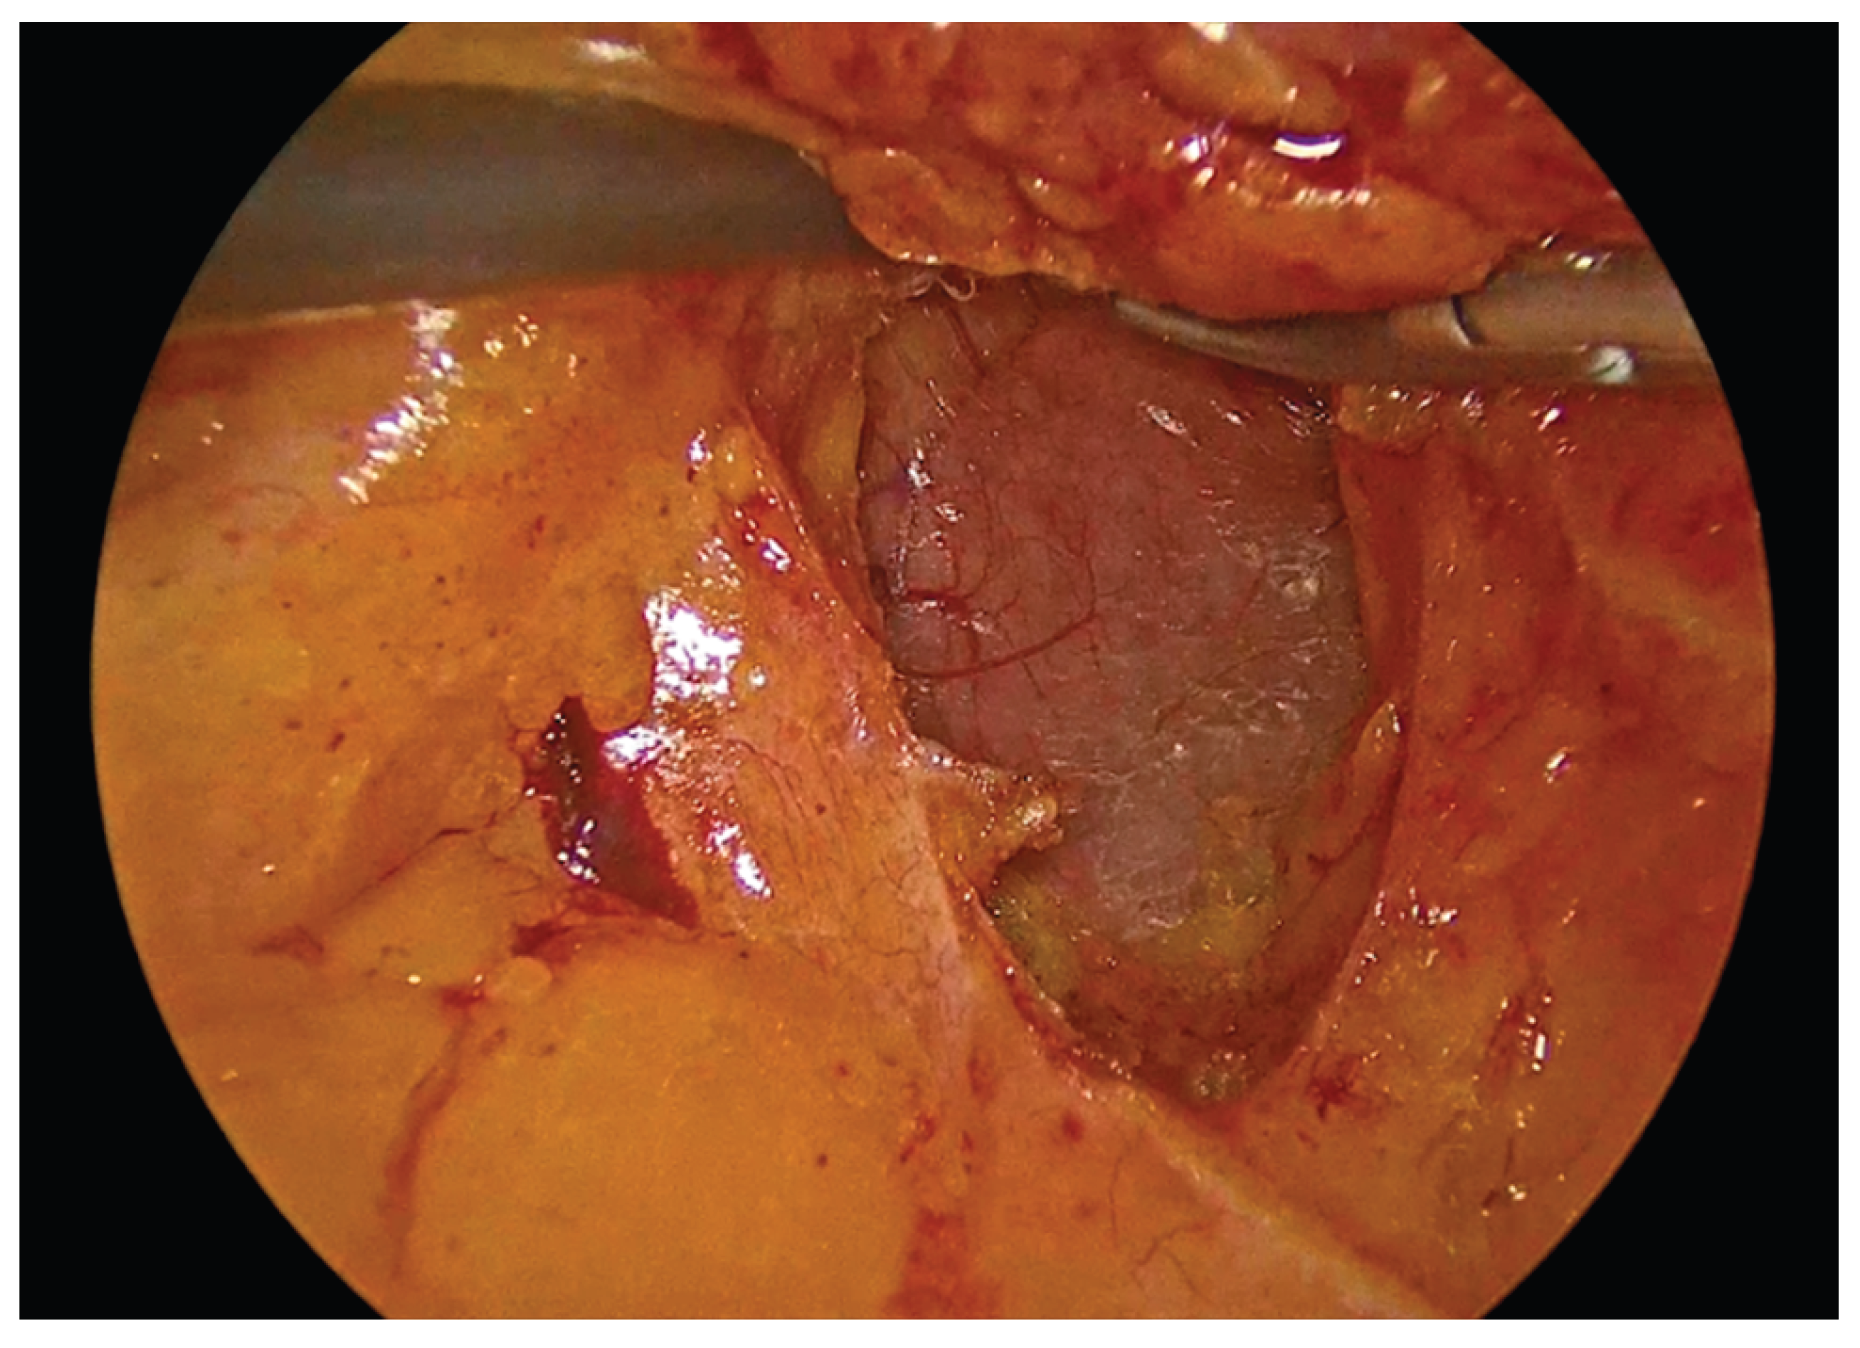

Figure 12. The completed single-layer handsewn intracorporeal anastomosis.

Preprints 195043 g012

In order to facilitate the ease of the construction of this anastomosis, we use right-hand, left-hand, back-hand, and fore-hand techniques. We take care not to evert the mucosa of the colon or ileum, but on the contrary to invert both mucosa into the suture line. We also try to be precise with the sutures and as far as possible the anastomosis to be symmetric. Completion of the anastomosis is followed by meticulous inspection of the suture line and stapled bowel ends to ensure adequate hemostasis and the absence of hematoma formation.